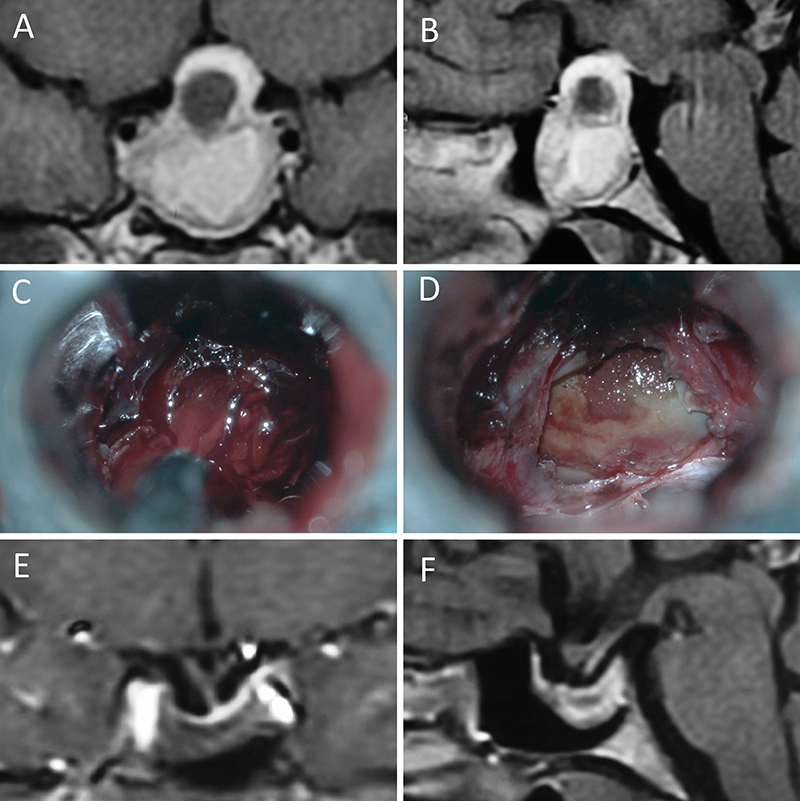

Figura 5: Apoplejía hipofisaria hemorrágica en un hombre de 32 años. El paciente presentó cefalea y parálisis completa del III par. Tuvo restitutio ad integrum en el seguimiento. A-B: RM preoperatoria; C-D: intraoperatorio; E-F: RM postoperatoria.

Figura 6: Apoplejía hipofisaria hemorrágica en un hombre de 55 años. El paciente presentó cefalea, déficit visual y parálisis completa del III par. Evolucionó favorablemente tras la cirugía, revirtiendo el cuadro. A-B: RM preoperatoria; C-D: intraoperatorio; E-F: RM postoperatoria.